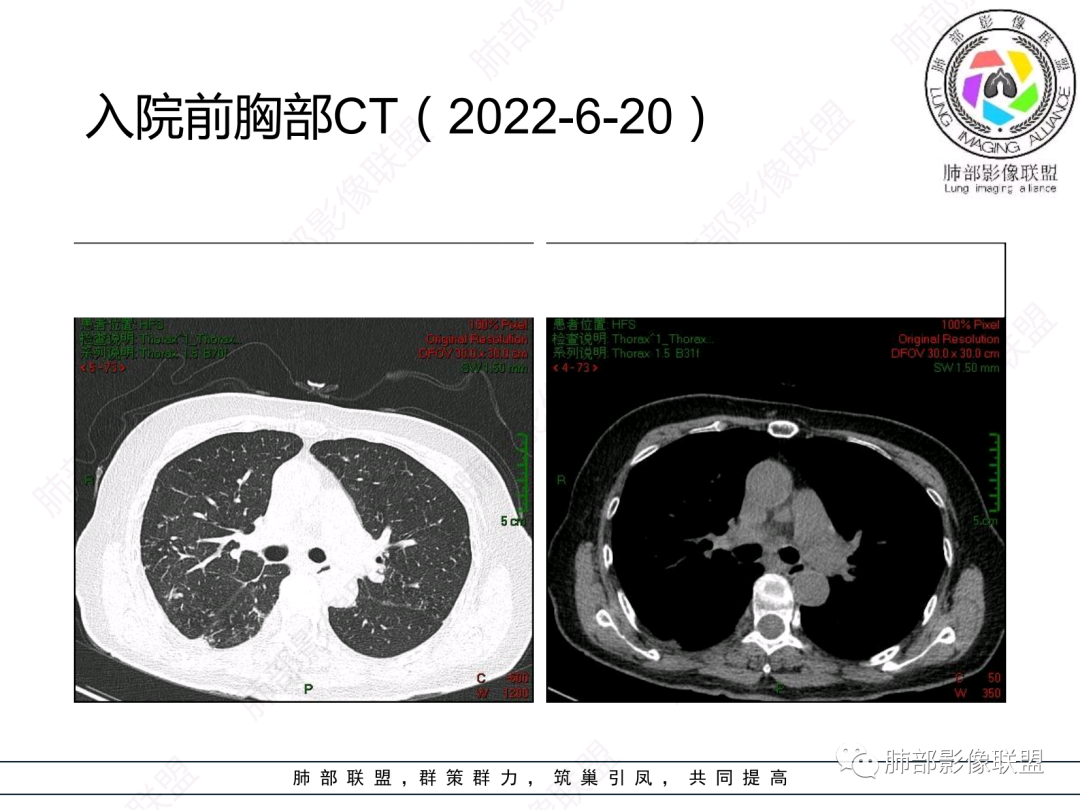

更正一下入院时间,2022-6-20

晨读:女,74,反复咳嗽咳痰6年,加重2月。血沉增快。胸部CT:左肺上叶团片影;左肺下叶团片影,内可见支气管扩张、小空洞,周围卫星灶;两肺多发结节、树芽征,可见支气管管壁增厚。考虑:TB?NTM?鉴别曲霉、DPB等。